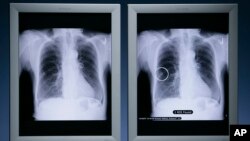

د روغتیا نړیوال سازمان د سرطان ناروغۍ د نړیوالې ورځې پرمهال د سینې سرطان په وړاندې چې له امله یې ګڼ شمیر میرمنې ژوند له لاسه ورکوي، د ډیرو اقداماتو غوښتنه وکړه.

هر کال څه باندې ۲.۳ میلیونه میرمنې د سینې سرطان په ناروغۍ تشخیص کیږي او کابو ۷۰۰ زره یې د همدې ناروغۍ له امله ژوند له لاسه ورکوي. په هغو هیوادونو کې د سینې سرطان میړینې زیاتې دي چې اقتصاد یې کمزوری دی.

د سرطان د متخصصینو په وینا، که د سینې سرطان په وخت تشخیص او تداوي نشي، دا ناوړه ناروغي به ډیر ژر په مرض اخته کس ووژني.